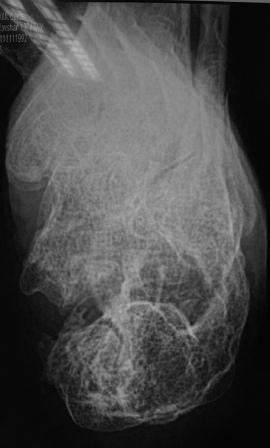

Вчера госпитализирован пациент 1970г.р., в ноябре 2014г, получил

о/перелом пяточной кости. в другой клинике произведена КДО аппаратом

Илизарова, после трех месяцев аппарат сняли, и больной начал наступать и

ходить, все это со слов больного (р-снимков нет.). Жалобы боль при

ходьбе, которая в динамике усиливается, об-но: деформация пяточной

кости, движение в г/стопном суставе почти в полном объеме, по медиальной

поверхности пятки рубец, плотно спаянный с костью.

Предварительный план: корригируюшая остеотомия пяточной кости, для

создания свода стопы (сможем ли опустить бугор пяточной кости из-за

натяжения ахиллово сухожилия), и подтаранный артродез.